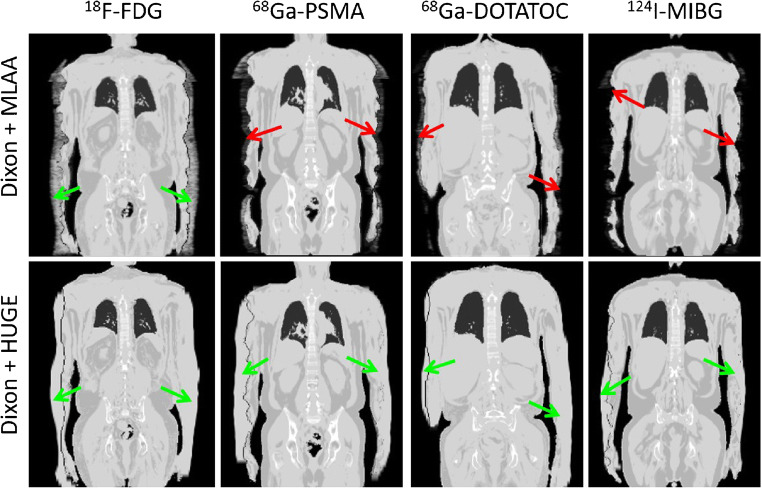

Figure 6 shows that the MLAA method in PET/MR with radiotracers 68Ga-PSMA, 68Ga-DOTATOC, and 124I-MIBG failed to provide accurate contours for attenuation correction. Particularly in the 124I patient example, the MLAA method did not add any linear attenuation coefficient to the standard Dixon-VIBE AC map. MLAA in PET/MR with 18F-FDG works robust, but reveals slight overestimations along the patients’ arms (green arrow). The truncation correction based on HUGE reveals a robust application along the patients’ arms with all 4 radiotracers and in all 23 patients and 28 examinations.

Fig. 6.

μ-maps with applied truncation correction due to PET-based MLAA (upper row) or MR-based HUGE (lower row) in four patient examples using four different radiotracers (18F-FDG, 68Ga-PSMA, 68Ga-DOTATOC, 124I-MIBG). Green arrows indicate accurate truncation correction, whereas red arrows indicate incomplete or failed truncation correction. Note that the MR-based HUGE method works robust, independent of the choice of radiotracer. MLAA provided acceptable truncation correction only in the patient example with 18F-FDG